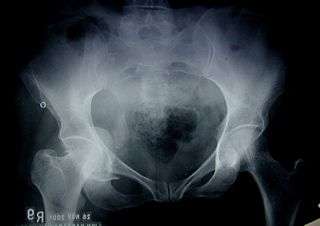

Fractures of the acetabulum occur when the head of the femur is driven into the pelvis. This is caused either by a blow on the side or by a blow in the front of the knee, usually in a dashboard injury when the femur also may be fractured.[1]

To understand fracture pattern it is essential to have minimum three x-ray views;

- · Pelvis with both hips antero posterior view

This view shows six important landmarks of the acetabulum, viz;

- 1. Pelvic brim

- 2. Ilio ischial line

- 3. Tear drop

- 4. Anterior wall

- 5. Posterior wall

- 6. Weight bearing dome